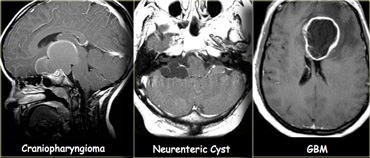

On the far left a craniopharyngioma with an enhancing rim surrounding the cystic component.

In the middle a neuroenteric cyst with the contents of which have the same signal intensity as CSF.

On the right a glioblastoma multiforme (GBM) with a central cystic component.

The enhancement in GBM is usually more irregular.